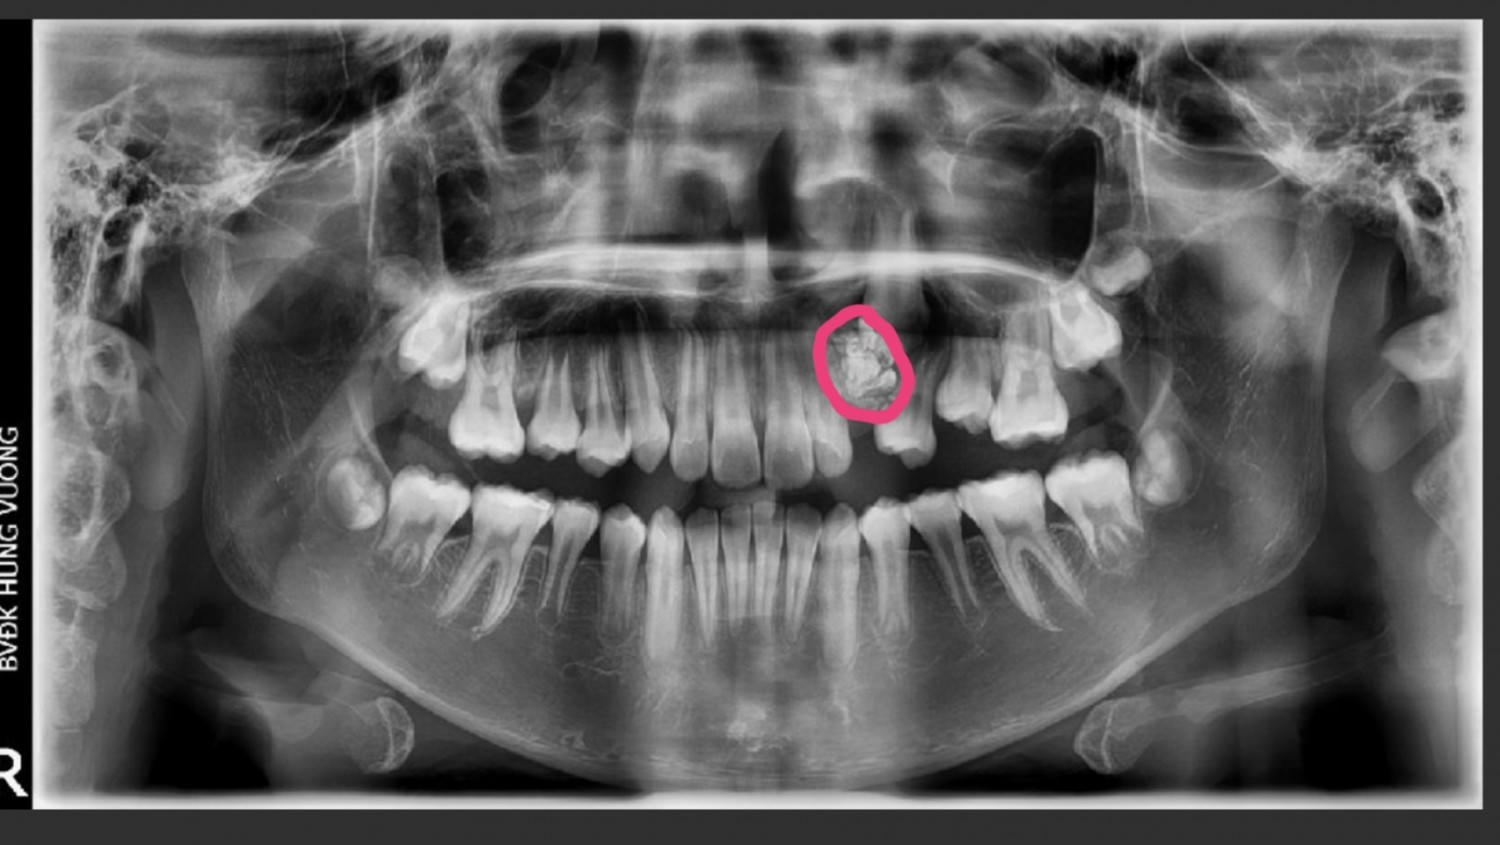

Được biết, bệnh nhân được gia đình đưa đến bệnh viện khám với lý do 12 tuổi nhưng răng nanh hàm trên bên trái vẫn chưa mọc. Kết quả chụp răng toàn cảnh của bệnh nhân cho thấy hình ảnh khối u răng kết hợp vị trí hàm trên bên trái.

Ngay lập tức, bệnh nhân được chỉ định phẫu thuật loại bỏ khối u răng. Trong quá trình phẫu thuật, các bác sĩ lấy ra gần 20 chiếc răng nhỏ tại khối u có đầy đủ thân, tủy và chân răng. Sau đó, bác sĩ đã thực hiện đặt khí cụ kéo răng nanh ngầm về đúng vị trí.